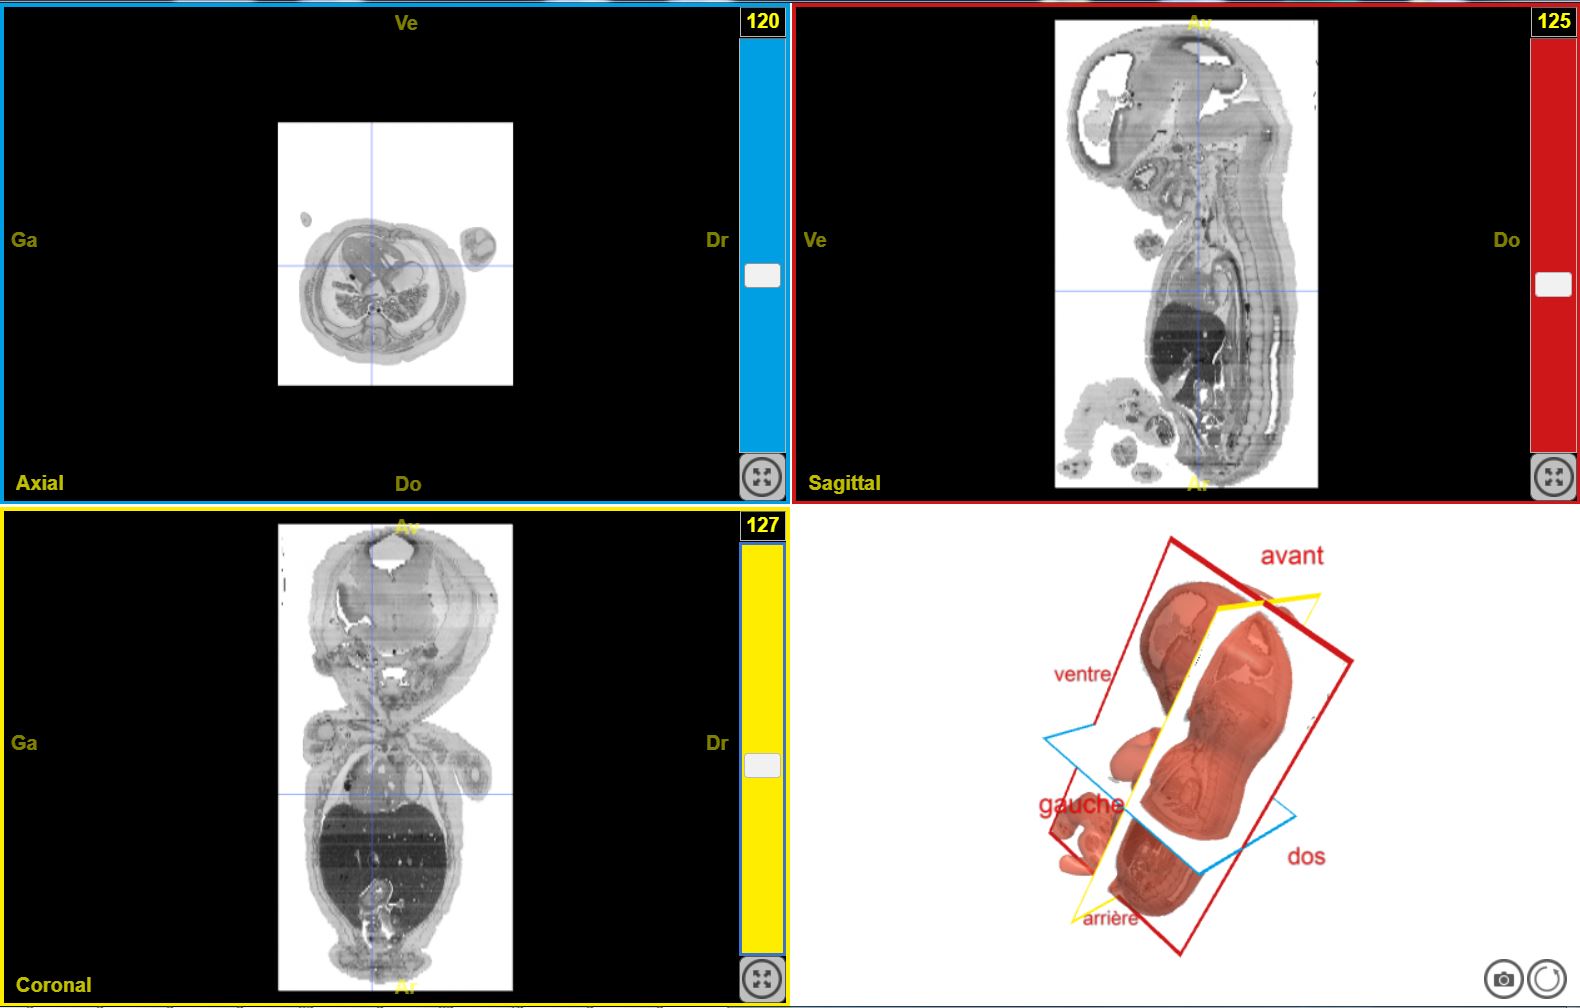

Carnegie EduAnat2 stade7